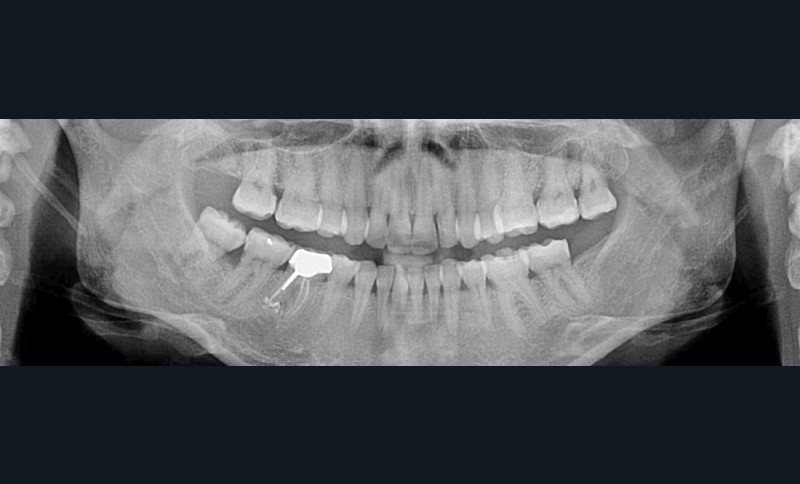

C’est précisément le cas de cette patiente de 33 ans qui présente une classe II squelettique par rétrognathie mandibulaire sur un schéma vertical hyperdivergent associée à une classe II/1 dentaire avec DDA par excès et biproalvéolie. Son profil est convexe, cis-frontal et, sur le plan fonctionnel, on peut observer une dysfonction linguale et une incompétence labiale au repos. Il en résulte une contracture des muscles de la sphère péri-orale lèvres jointes. La formule dentaire n’est pas complète puisque les quatre deuxièmes prémolaires ont été extraites lors d’un premier traitement orthodontique et qu’il y a également agénésie des troisièmes molaires 18 et 38 (fig 1 à 11).

Au regard de ces éléments, la décision thérapeutique choisie intègre une prise en charge orthodontique associée à une chirurgie orthognathique d’avancement mandibulaire et à une mentoplastie. L’étape initiale du traitement orthodontique consiste en la levée des compensations dentaires qui se traduit par la correction de la proalvéolie mandi– bulaire dans le but de pouvoir corriger la classe II squelettique et dentaire par avancement chirur- gical de la mandibule. Pour cela, des mini-vis d’ancrage sont positionnées distalement aux secteurs 3 et 4, enfouies à la base des branches mandibulaires avec des chaînettes métalliques émergentes dans la cavité buccale. L’objectif est d’assurer le repositionnement incisif mandibulaire grâce à des modules élastiques.